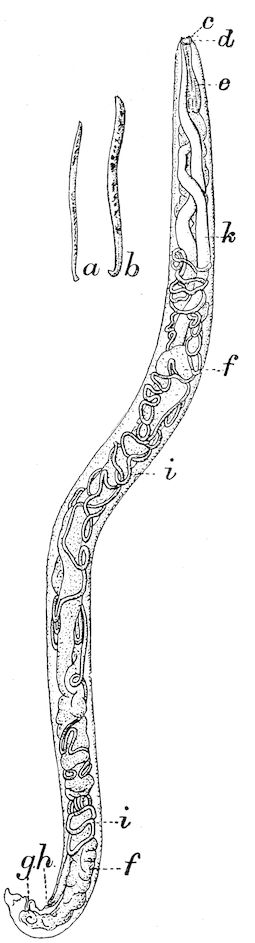

| VIII. | PARASITES OF THE DIGESTIVE APPARATUS | 263 | ||

| Gastro-intestinal strongylosis in sheep | 263 | |||

| Lumbricosis of calves | 267 | |||

| xi | Strongylosis of the abomasum in the ox | 268 | ||

| Parasitic gastro-enteritis, diarrhœa, and anæmia in cattle, sheep and lambs | 268 | |||

| Intestinal coccidiosis of calves and lambs (Psorospermosis, hæmorrhagic enteritis, bloody flux, dysentery, etc.) | 271 | |||

| Intestinal helminthiasis in ruminants | 275 | |||